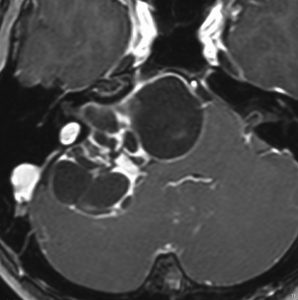

聴神経腫瘍や三叉神経鞘腫と間違えそうな顔面神経鞘腫

20代の男性で,下顎と口腔内の軽度の感覚以上だけがありました。聴力は正常で顔面神経麻痺は全くありません。でもこれは巨大な顔面神経鞘腫です。手術前は三叉神経鞘腫を疑っていました。

内耳道が少し拡大して内耳道内にも腫瘍があります。

手術摘出しましたが,聴神経は正常に見えて手術後も聴力は保たれました。三叉神経からは完全に剥離できています。

腫瘍の外側表面で顔面神経は紙のように薄くなって(菲薄化して),モニターで位置を確かめながらのかなり難しい手術となりました。